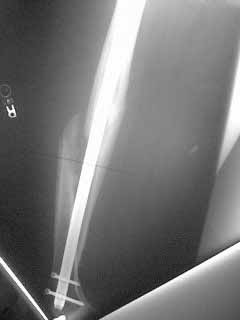

Pt is 27 yo construction worker now 5 months post fx. He has tenderness localized over distal locking screw heads. CT confirms bridging bone posteriorly. How much healing is necessary? Suggestions for further management are appreciated.

I don't think the distal screws really are the source of pain. The image doesn't show proximal screws - is the nail dynamized or statically locked? If the latter i would remove the proximal static screw and leave the patient for 4-6 months or forever if he becomes asymptomatic.

1. If the # is not dynamised dynamise by removin the distal lockin.

2. Consider bone grafting the gap in the distal femur where the spiral looks displaced.

I can't dynamise the nail by removing the distal locking because of its spiral fracture line. Dynamise will be unstable to the fracture. And the case has tenderness in the distal locking region . It may be refracturearound the distal hole . I don't want to use bone grafting because it will disturb the soft tissue and may not be good to fracture healing.

So I think it will be better to identify whether there is refracture around the distal hole .If so , I think it will be better to remove the nail and a LISS can be used.

From what you say, I'd be slow to do anything fast - certainly not remove screws or bone graft yet - 5 months is not very long since injury, especially if he's still healing. I'd review serial, better quality x-rays. Not just AP & Lat, but both obliques as well. I'm assuming he's fully weightbearing a, has good motion and is progressing satisfactorily with rehab, and that his "locking screw head pain" is tolerable. If he fails to progress, or has significantly limited activity, then perhaps suspect nonunion or structural insufficiency. Does the anterior bone prominence bother him? Knee motion ok? Isn't there some new bone in the anterior gap?

I did get CT which confirms union along the posterior cortex.

The crutch means that the pain depends on loading of the limb. So it must be cyclic motions somewhere in the nail-screws-bone interface during walking.

I doubt that locking screw pain would lead one to use a crutch.

This suggests that fx is not healed, or that union is tenuous.